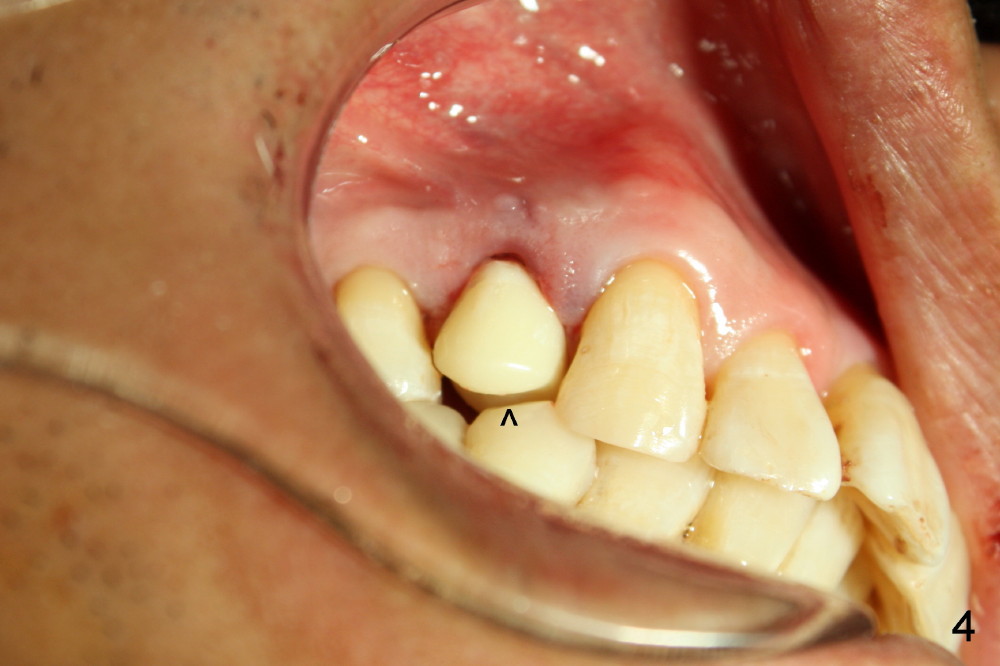

A provisional is fabricated immediately after extraction and implant and definitive abutment placement (Fig.3,4: P). The provisional hold the papilla in place (Fig.3 *). There is no occlusal contact with the opposing dentition (Fig.4 ^). The gingiva looks purplish due to difficult extraction. The tooth keeps fracturing while being extraction. The bone is dense. On the other hand, the dense bone helps achieve primary stability of the implant.